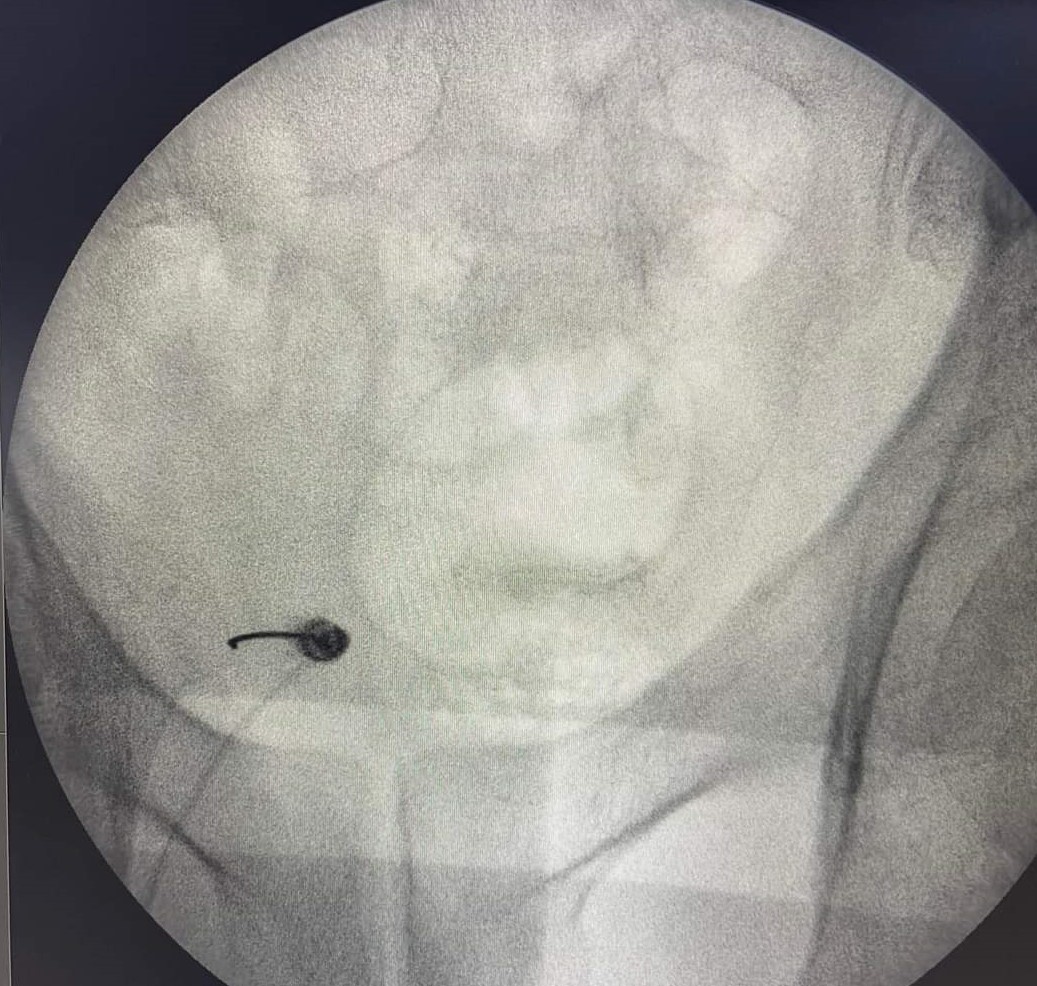

- Νευρόλυση με χρήση παλμικής ραδιοσυχνότητας υπό ακτινοσκοπική καθοδήγηση

- Φαρμακευτικό block με στεροειδή και τοπικό αναισθητικό